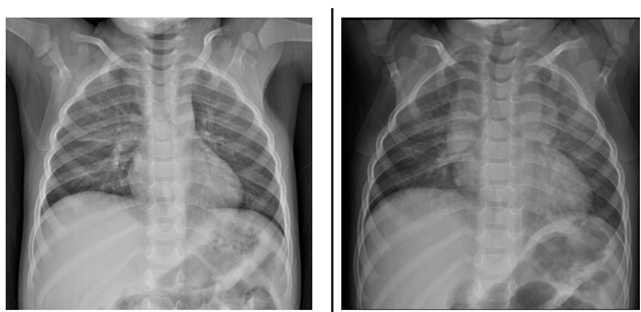

Menino de 2 anos e 6 meses, com história de tosse, dispneia, choro, inapetência e febre há 4 dias, realizou radiografa de tórax (primeira imagem). Após o exame, a mãe recebeu receita médica com medicações para a criança tomar durante 2 semanas, com orientação de repetir a radiografa (segunda imagem) 1 semana após o término do tratamento.

( ) O diagnóstico inicial mais provável é pneumonia, tanto pelos dados clínicos como pela presença de opacidades pulmonares no terço médio à direita na primeira imagem, porém o achado de massa mediastinal na segunda imagem torna a hipótese de pneumonia menos provável.

( ) No exame de controle evolutivo realizado 3 semanas após o primeiro atendimento houve o aparecimento de consolidações pulmonares supra-hilares bilaterais, indicando piora radiológica.

( ) Após a análise das duas radiografas, pode-se chegar à conclusão de que trata-se de um quadro de hiperplasia tímica rebote em criança em processo de recuperação de pneumonia.